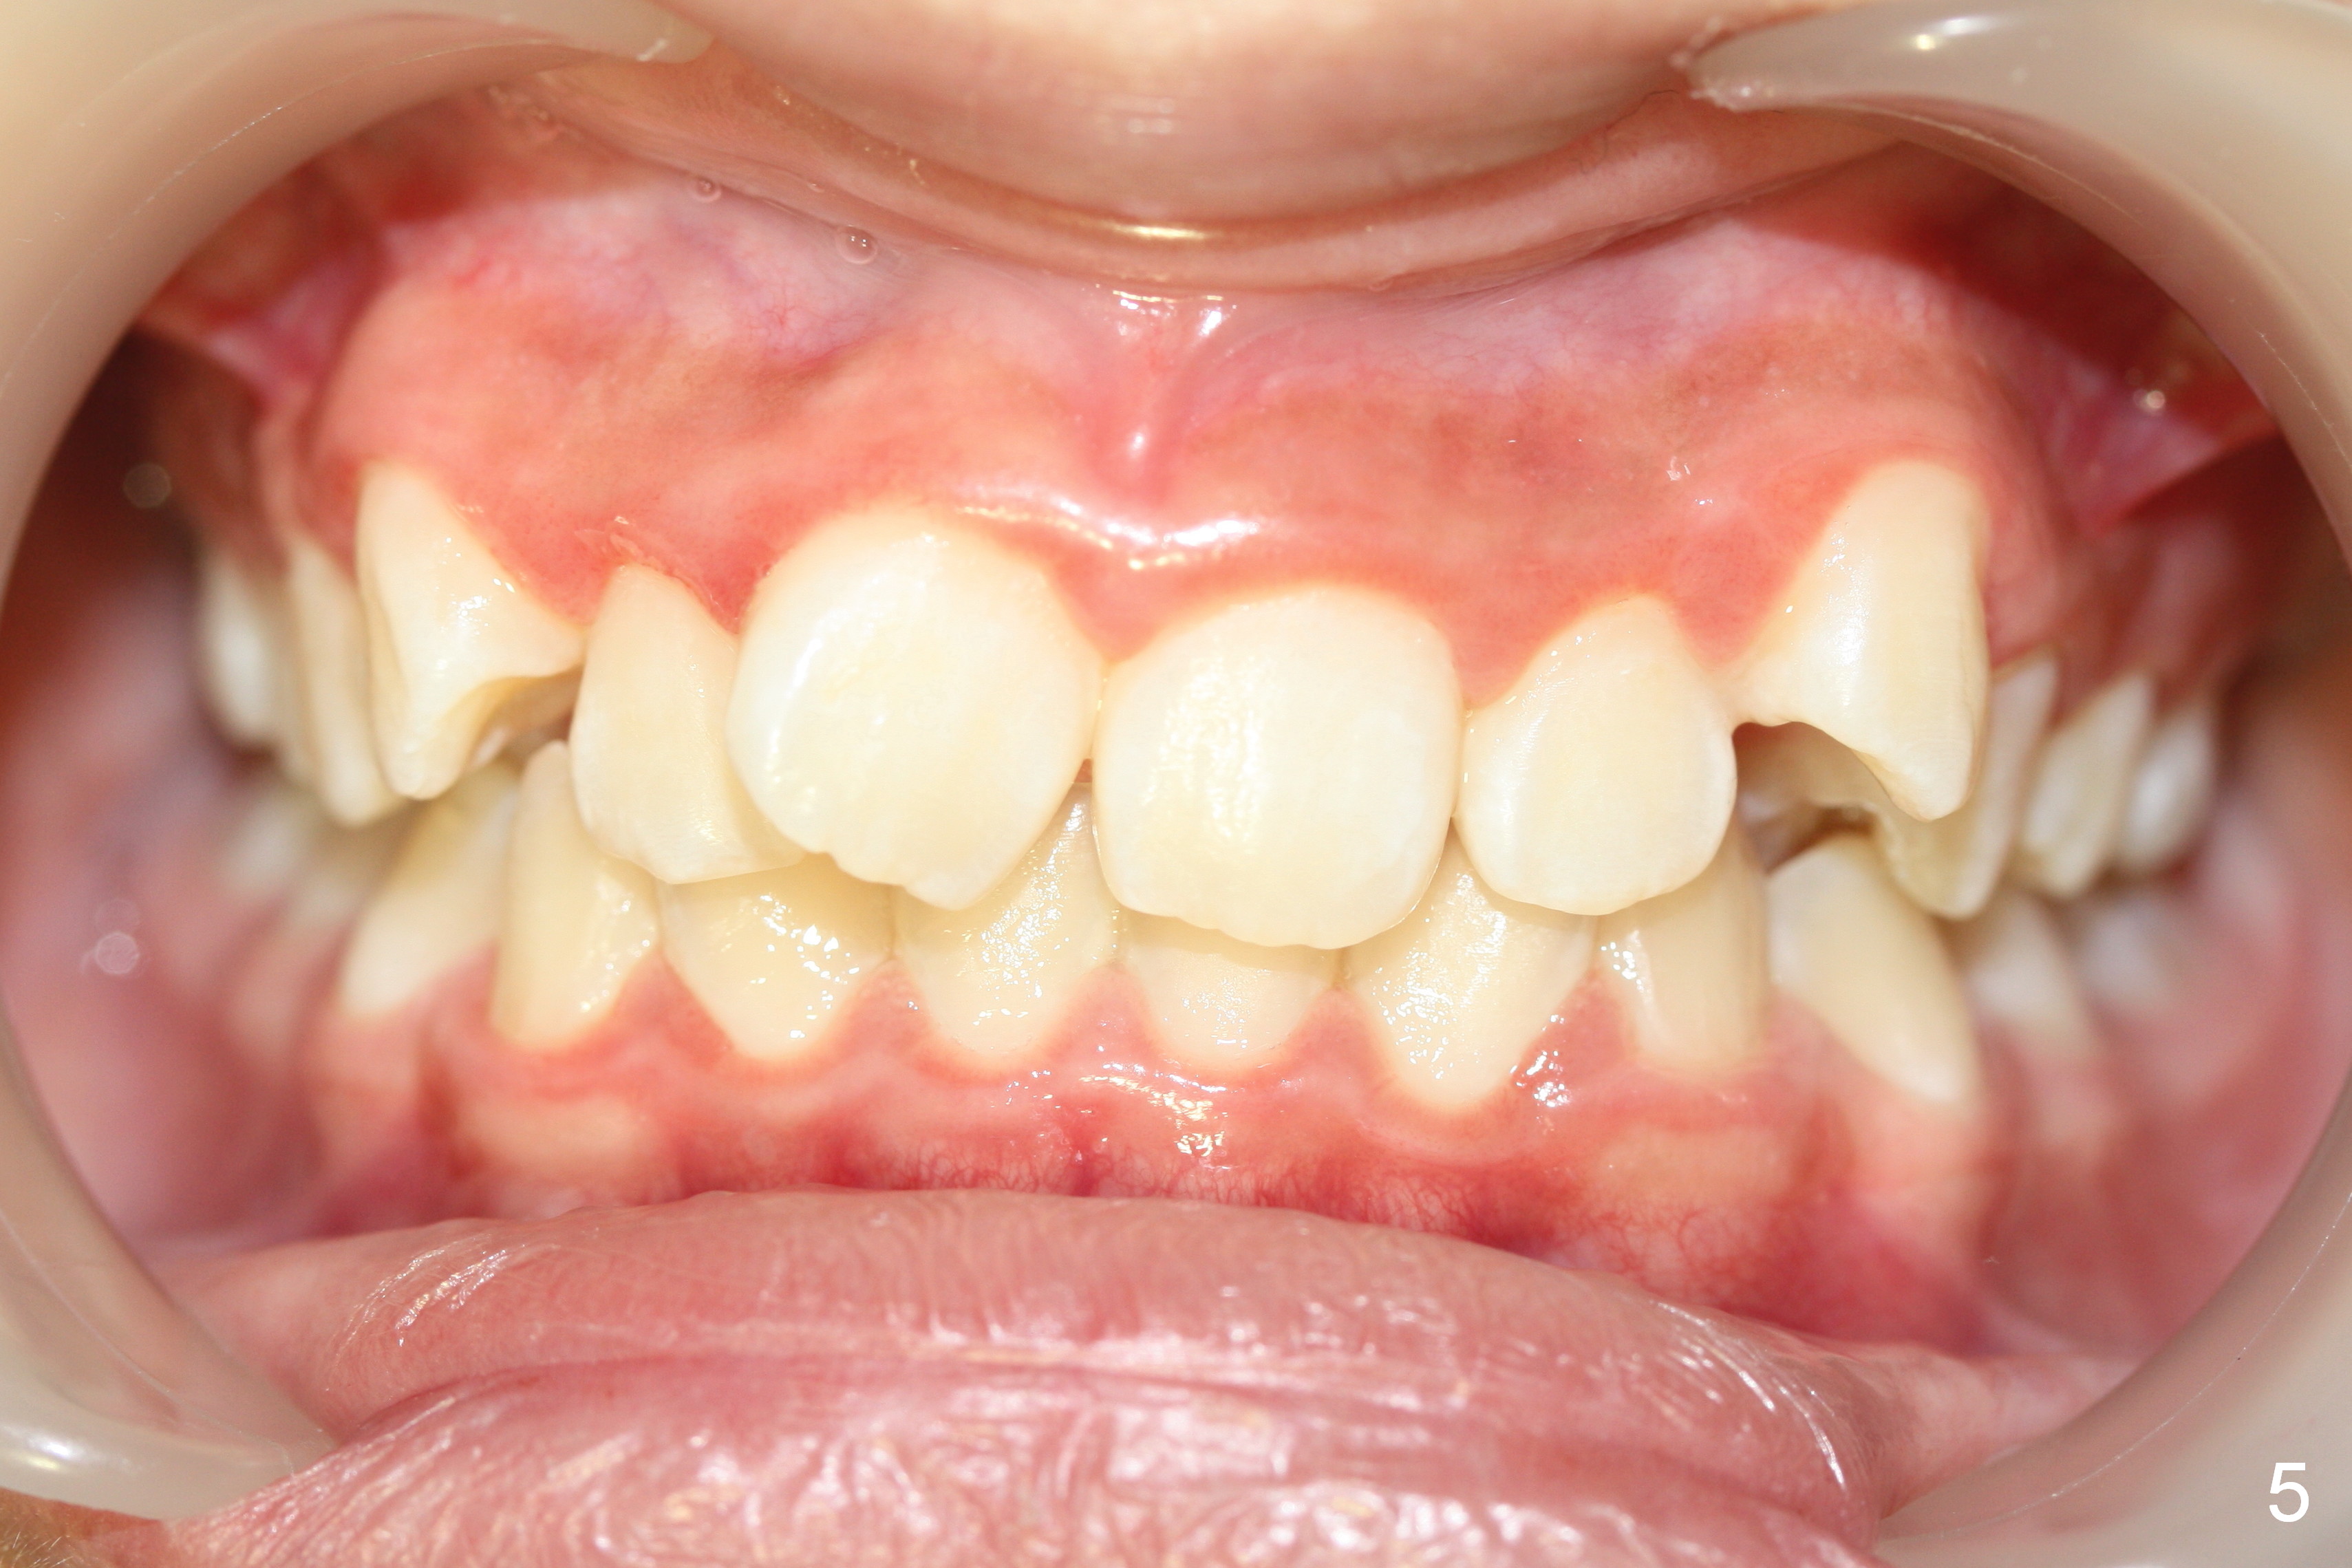

A 12-year-old girl has Class II Division I malocclusion (Fig.5,6) with protrusion of the upper lip (Fig.3). With extraction of the upper 1st bicuspids, postop facial profile improves (Fig.3', 4').

Make sure that the camera is parallel to the imaginary occlusal plane (Fig.5') when intraoral occlusal frontal view is being taken.